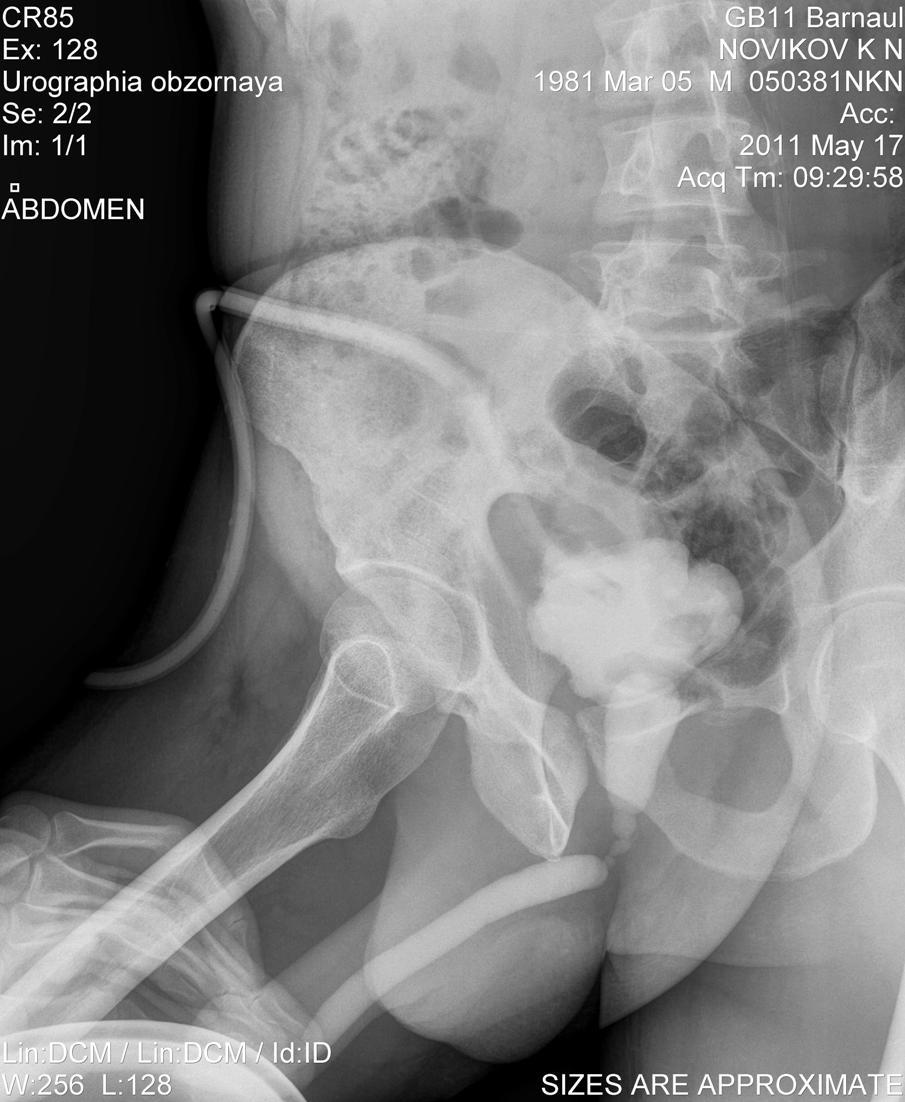

Здравствуйте! Мужу недавно сделали цистостомию, поставили диагноз: стриктура уретры (стриктура бульбозного отдела уретры около 2х см.)Стоит вопрос о "Открытой реконструктивной операции на уретре" у нас в г. Барнауле либо в Москве. Скажите пожалуйста какова вероятность успеха данной операции и как долго нужно будет находиться под наблюдением врачей, так же интересует возможно ли иное лечение при данном течении заболевания. Лечащий врач советует делать операцию в Москве, подскажите пожалуйста возможна ли бесплатная опреация, т.к. муж основной кормилец в семье, у него трое иждевенцев, я и двое детей 1 и 3 лет, наш семейный бюджет просто не потянет такую сумму. Прикрепляю фото последней уретрографии и выписку из поликлиники с точным диагнозом. Заранее большое спасибо!